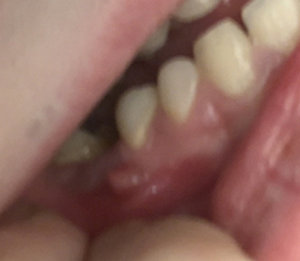

Подскажите, пожалуйста. Болела десна около недели, незначительно. Позже образовался какой-то шарик, похожий на прыщик. А после, во время еды что-то стало мешать и вот появилось непонятное новообразование из десны. На ощупь твердое, беспокоит во время приема пищи.

Подскажите, что это может быть?

Очень сложно определить, но все Ваши симптомы говорят и свищевом выходе. То есть, на верхушках зуба имеется воспалительный процесс.

Необходимо обратиться к врачу, сделать рентген-снимки и выявить точную причину.